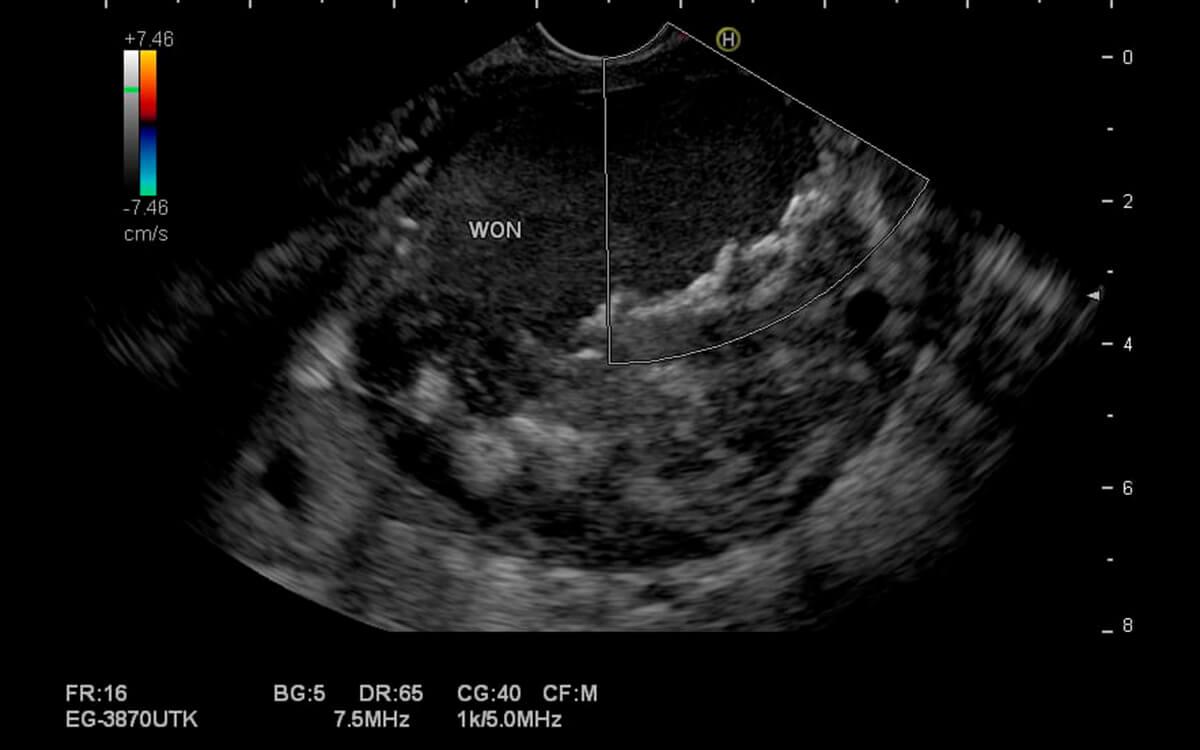

- Ecoendoscopia

Como é feito o procedimento de ecoendoscopia ?

O exame ecoendoscopia tem duração média de 30 minutos e o modo é feito é muito semelhante ao de uma endoscopia convencional quando o exame for do trato digestivo alto, ou semelhante à colonoscopia, quando o exame for do trato digestivo baixo.

A ecoendoscopia é feita com 02 médicos em sala, o endoscopista e o anestesista, sendo o primeiro dedicado ao exame e o segundo dedicado à sedação e conforto do paciente. O exame de ecoendoscopia só poderá ser iniciado quando o paciente estiver devidamente posicionado, monitorizado e após a realização da sedação endovenosa, entrar em estado de sono tranquilo. Essas condições garantem que não haverá nenhum desconforto ou dor.

Então, o médico endoscopista, devidamente paramentado, introduz o aparelho de ultrassom endoscópico por via oral (quando o exame for da parte alta) ou por via retal (quando o exame for da parte baixa), lubrificado imediatamente antes para reduzir atritos.

Por todo esse contexto, o exame de ecoendoscopia é considerado um exame seguro e minimamente invasivo, não devendo gerar preocupações excessivas nos pacientes.

Durante o exame é possível ainda realizar procedimentos terapêuticos e a coleta de pequenos fragmentos de tecidos, com pinças para biópsia ou punção por agulha, sendo que esses materiais serão enviados posteriormente para análise anatomopatológica em laboratório.